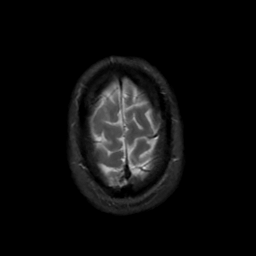

MR Study #6, March 17, 1991 -- Slice #45

[Home][Help][Clinical][Tour 1][Tour 2] Slice 45